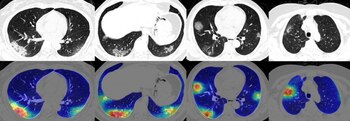

Y a diferencia de estos dos modelos, el llamado COVID-Net, que se hizo público el 24 de marzo, es de acceso abierto para que todos los investigadores del mundo que lo deseen puedan perfeccionar una herramienta de IA para detectar la enfermedad que causa el SARS-CoV-2.

“COVID-Net es una red neuronal convolucional”, explicó MIT Technology Review. “Desarrollada por Linda Wang y Alexander Wong en la Universidad de Waterloo y la empresa DarwinAI en Canadá, COVID-Net fue entrenada para identificar signos de COVID-19 en radiografías de tórax a partir de 5.941 imágenes tomadas de 2.839 pacientes con diversas condiciones pulmonares, incluyendo infecciones bacterianas, infecciones virales causadas por otros agentes y por COVID-19. El conjunto de datos se proporciona junto con la herramienta para que los investigadores, o cualquiera que quiera retocarlo, pueda explorarlo y ajustarlo”.

Según el estudio que la presentó, esta red tiene por fin “impulsar el desarrollo de soluciones de aprendizaje profundo muy precisas y prácticas para detectar los casos de COVID-19 y acelerar el tratamiento de aquellos que más lo necesitan”.